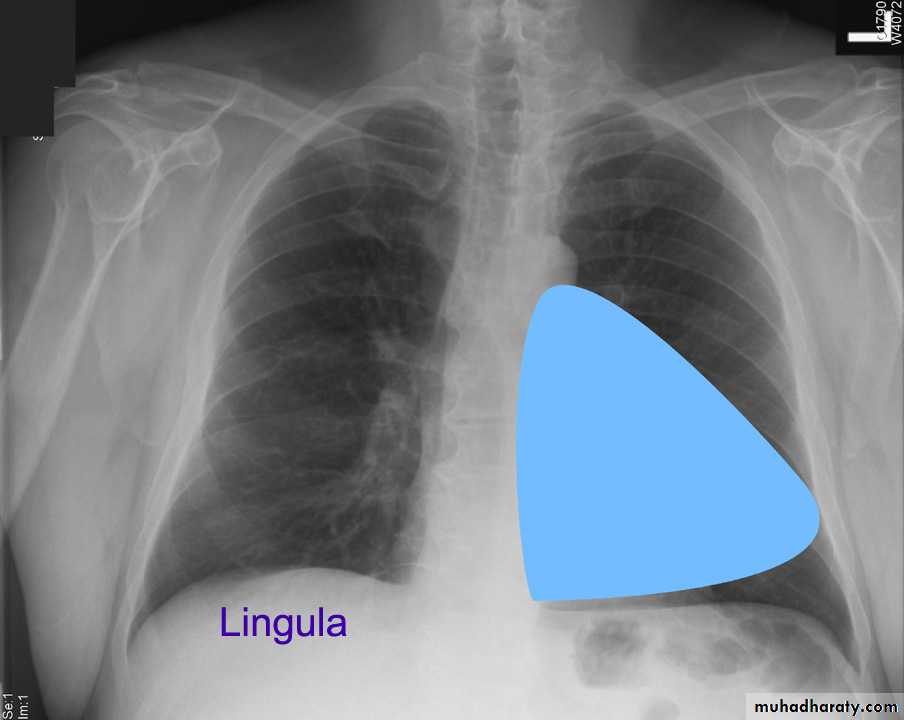

Lung Anatomy

Zonal anatomyLobar anatomy

Rt lung divided to 3 lobes (upper , middle & lower )

Transverse fissure separate the upper lobe from middle lobeOblique fissure separates the upper & middle from lower lobe .

The left lung subdivided to two lobes by oblique fissure ( upper & lower )

Rt upper lobe

Rt middle lobe

Rt lower lobe

Left upper lobe

LUL collapse

Left lingula

Left lower lobe